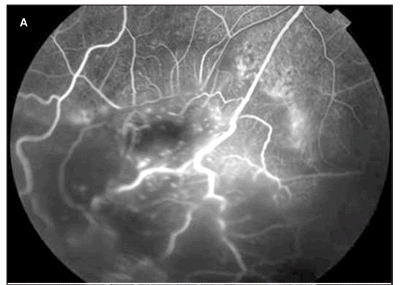

A angiofluresceinografia evidenciou enchimento precoce na fase arterial (Figura 2A) e, no decorrer do exame, extravasamento de contraste pelos vasos incompetentes (Figura 2B) com hiperfluorescência tardia em toda lesão (Figura 2C). Não foram detectadas áreas de exclusão capilar. Foi observada também hiperfluorescência na região foveal, que aumentou durante o exame no OD (Figura 3). Não foi demonstrada qualquer alteração no OE.